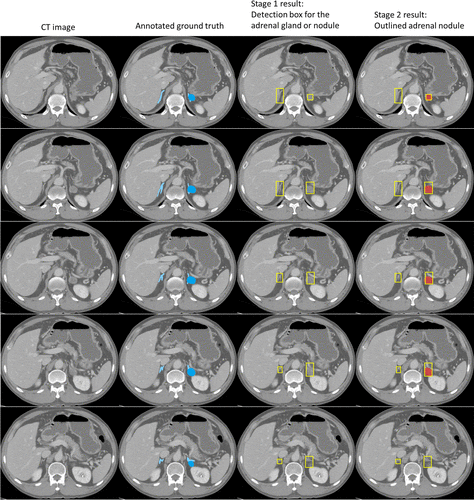

Another story connects medicine and computation from a different angle. A study from RSNA researchers shows that AI models can read chronic stress from routine chest CT scans. The model measures adrenal-gland volume. The adrenal glands control hormones tied to stress and metabolism. Oversized glands signal sustained stress exposure.

Researchers compared gland measurements against cortisol levels, BMI, blood pressure, and patient-reported stress. The results matched across metrics. The model flagged long-term stress responses in thousands of scans. One researcher stated the impact: AI reveals the “long-term burden of stress inside the body” with tools hospitals already use.

The model proposes a door into silent risk categories: heart failure, depression, metabolic strain. It even creates a consistent measure across large patient groups — something questionnaires and cortisol spikes never delivered cleanly. The study notes that poor scans create poor outcomes, so clinicians confirm AI suggestions. But the core insight stands: AI-assisted medical imaging identifies stress as a biological structure, not a mood.